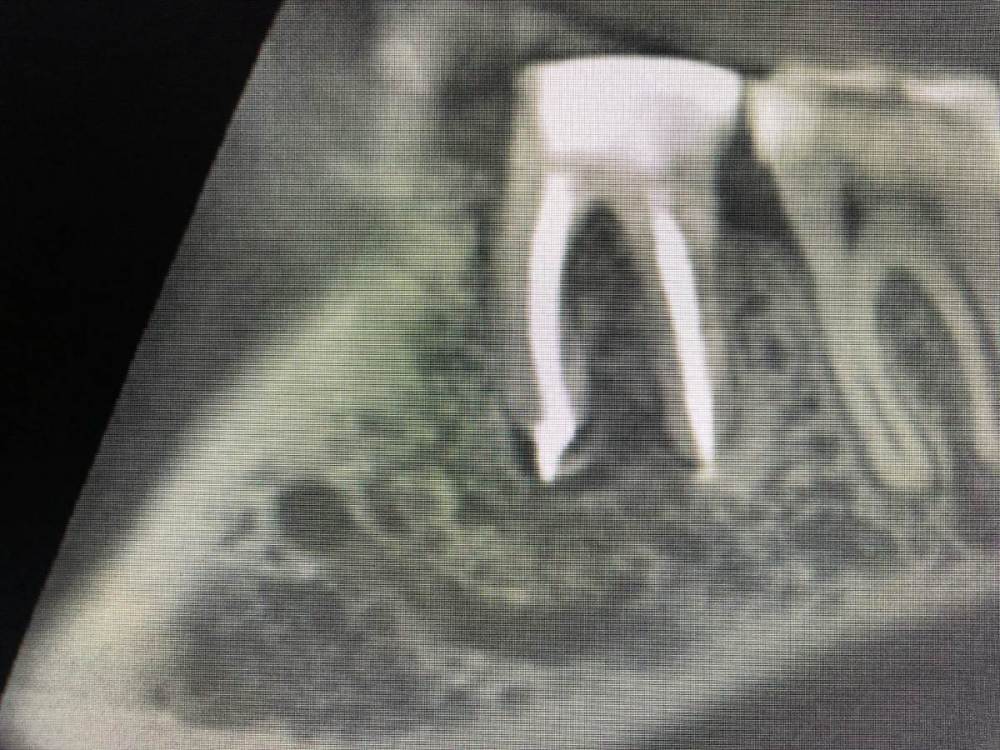

Вторичная эндодонтия 3.6 с лизисом кортикальной пластинки щечно